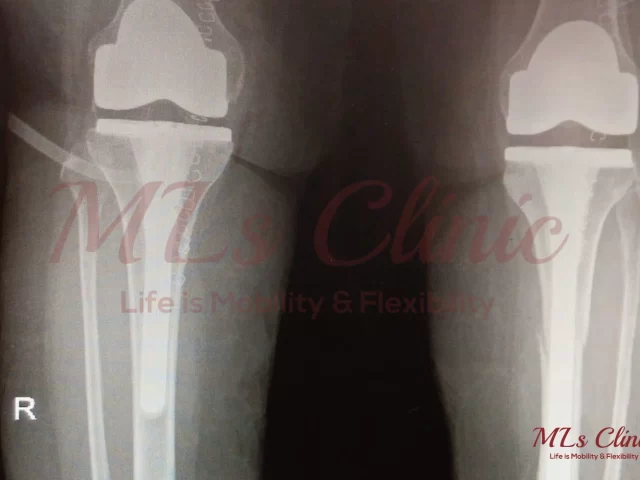

Two Knees, One Solution: Understanding Bilateral Knee Replacement.

Are you struggling with pain in both knees due to arthritis or joint degeneration? You’re not alone. Many people suffer...

Knee Implant Materials: Titanium, Cobalt, Zirconia – Finding the Best Fit for You!

Are you also the one who is suffering from constant Knee Pain? Are you the one who has been told...